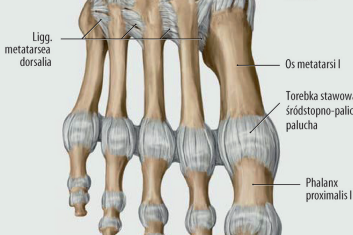

Terapia stawu krzyżowo-biodrowego

Testy i techniki terapii manualnej opisane w tym artykule są bardzo przydatne w celu zidentyfikowania problemu, ustalenia planu terapeutycznego i...